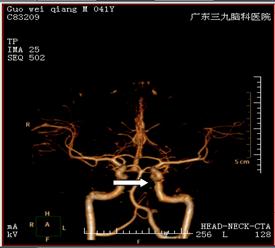

两日后,患者转入广东三九脑科医院,入院时查体:血压147/96mmhg,意识清楚,不完全运动性失语,口角左歪,肌张力正常。DSA影像显示:左侧颈内动脉颈段重度狭窄,左侧大脑中动脉经后交通代偿,其余血管未见明显异常(图二)。

治疗前MRA(图一) 治疗前DSA(图二)